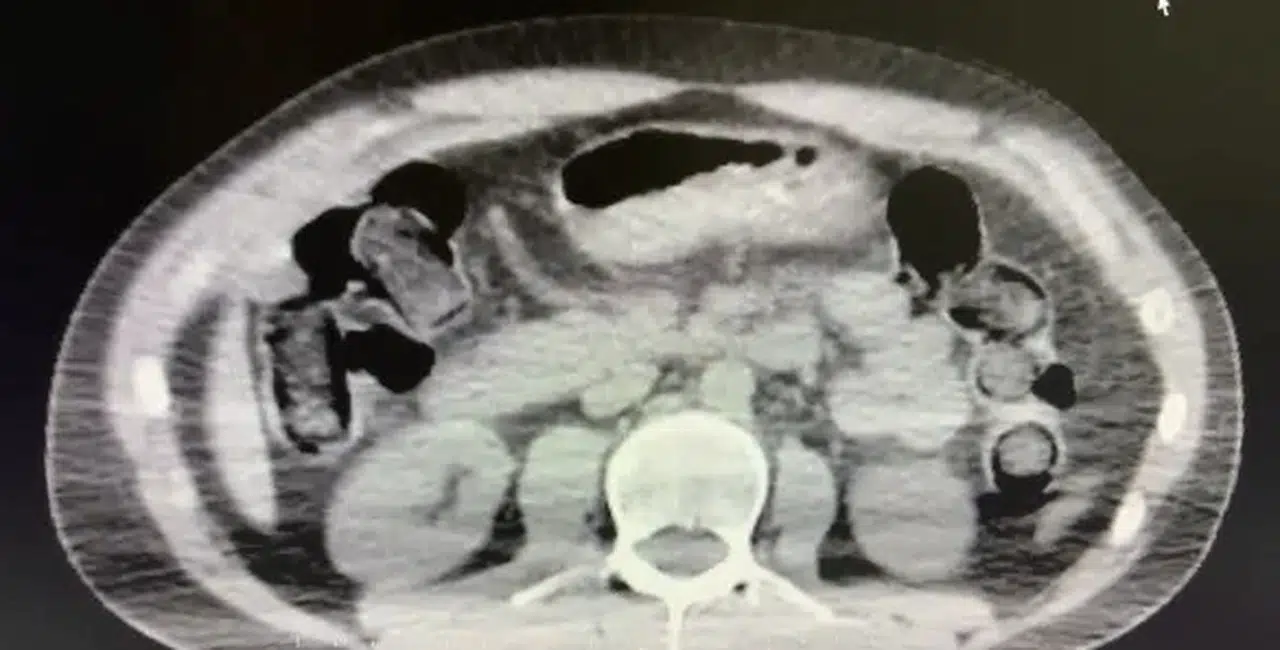

Şüphelilerin ikametlerinde ve araçlarında yapılan aramada 101 kapsül halinde 722 gram uyuşturucu madde, 1 adet hassas terazi, uyuşturucu madde sevkiyatında yutma yönteminde kullanılan muhtelif materyaller, uyuşturucu madde ticaretinden elde edilen 20 bin 210 TL, bin 320 euro ve 10 ABD doları ele geçirildi. Emniyetteki işlemlerinin ardından adliyeye sevk edilen 2 şüpheli, çıkarıldıkları mahkemece tutuklanarak cezaevine gönderildi.